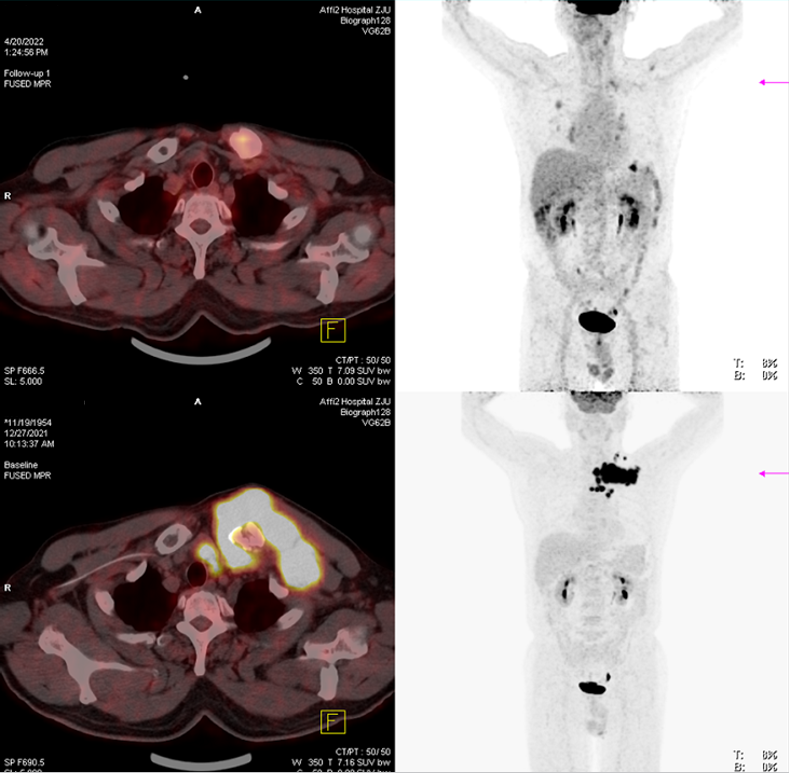

➤CAR-T回输后3个月的疗效评价-完全缓解:2022-4-20,阿基仑赛回输后3个月行PET-CT检查

示左锁骨胸骨端病理性骨折伴周围软组织肿块,原左颈部、左锁骨区、胸骨后、胸骨左缘多发肿大淋巴结较前代谢减低,软组织及淋巴结基本未见;胸8左侧附件、腰3椎体骨质破坏,糖代谢不高,上述均考虑治疗后完全缓解(CR)。

CAR-T细胞治疗后复查(上:2022-4-20,下:2021-12-27)